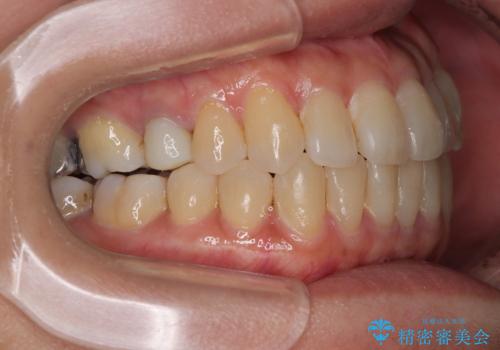

- 前歯のデコボコや八重歯を治したいとのことで来院された患者様です。

受け口傾向の骨格であり、前歯はクロスバイトまたは切端咬合となっており、下顎を中心に歯列全体の後方移動を行い、IPR(歯と歯の間を削る)によってデコボコが解消するように設計し、インビザラインにより治療を行うこととしました。

受け口傾向のインビザライン矯正は比較的治療を行いやすいため、きれいに仕上げることができました。舌の突出癖が顕著であったため、改善のためのトレーニングをしっかりと行っていただきました。